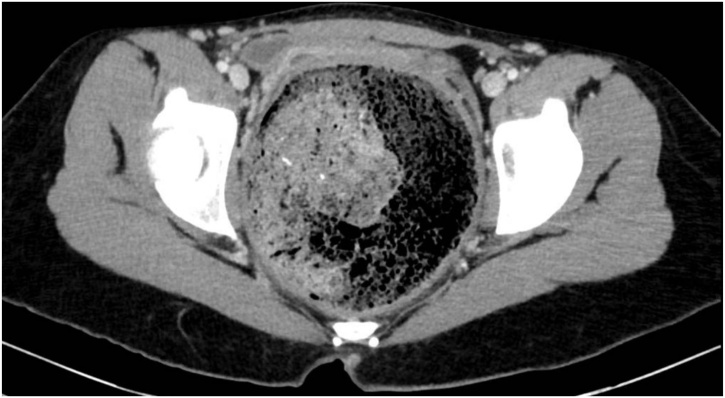

A 19-year-old Caucasian female patient was referred to General Surgery Department after her PCP found megacolon and megarectum in a computed tomography (CT) scan of the abdomen and pelvis (Fig. 1, Fig. 2, Fig. 3). Her evaluation and diagnostic procedures were performed by a board-certified general surgeon with colorectal surgery training. She had a lifelong history of intermittent abdominal pain as well as constipation requiring daily laxatives and enemas. Other than that, she did not have a history of medical or surgical problems. She did not smoke and her family history was unknown since she was raised by her aunt. Her abdominal exam was within normal limits. Her ano-rectal exam was normal on inspection, the digital rectal exam demonstrated a normal resting tone as well as hard stool in the rectal vault. The CT scan was significant for a severely distended sigmoid colon and rectum. Her lab work included a complete blood count and a comprehensive metabolic panel, these were within normal limits. Given her presentation the work up included: colonic transit study (Fig. 4), barium enema (Fig. 5) and a full thickness rectal biopsy after rectal de-impaction. Anal manometry was not performed. The colonic transit study (Sitz Marker Test) displayed most of the markers in her sigmoid colon and rectum at day number five. The Barium enema showed similar findings to those of the CT scan which included a dilated rectum starting immediately above the anorectal ring. She was taken to the operating room for a rectal biopsy. Under general anaesthesia and in lithotomy position a manual de-impaction was performed followed by rectal irrigation and a full thickness rectal biopsy. An anoscope was used to identify the level of the target area. In order to include the submucosa 2 full thickness rectal biopsies at 1.5 and 3 cm from dentate line in the posterior aspect were taken. Distal and proximal to this location a 2-0 Vicryl full thickness traction stitch was placed. This allowed total control of the tissue to ensure full thickness specimens. Both defects were closed with running 2-0 Vicryl. The patient tolerated the procedure well; she was discharged home the same day on a soft diet and had no post-operative complications. Pathology results showed the lack of ganglion cells in the submucosa (Fig. 6a-b). Routine H&E staining, as well as Immunohistochemistry stains for S100, Smooth Muscle Actin (SMA) and Calretinin were performed. Both SMA and Calretinin were negative despite appropriate controls which confirmed diagnosis of Hirschsprung’s disease (Fig. 7a-b). The patient was then referred to a tertiary care center. The chief of Pediatric Surgery took over her case. She underwent manual fecal de-impaction, a confirmatory rectal biopsy, laparoscopic seromuscular sigmoid biopsies for levelling and a diverting loop ileostomy for decompression of the dilated colon and rectum. The distal sigmoid colon biopsy showed few ganglion cells; the proximal colon had a normal amount. Seven months later she underwent an uneventful laparoscopic proctectomy with perianal colo-anal pull through procedure of which she recovered well. The operation was uneventful. Two months later her loop ileostomy was closed. She has been doing well. She is having two bowel movements a day with very good control and no longer suffers from constipation.

Fig. 3.

CT scan showing megarectum and fecaloma in the axial section.